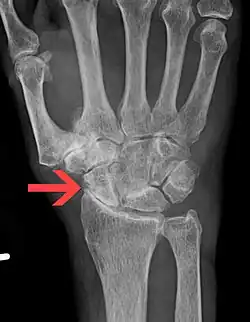

Diagnosis is made with reasonable certainty based on history and clinical examination.[42][43] X-rays may confirm the diagnosis. The typical changes seen on X-ray include: joint space narrowing, subchondral sclerosis (increased bone formation around the joint), subchondral cyst formation, and osteophytes.[44] Plain films may not correlate with the findings on physical examination or with the degree of pain.[45] Usually other imaging techniques are not necessary to clinically diagnose osteoarthritis.

X-ray of erosive osteoarthritis of the fingers, also zooming in on two joints with the typical "gull-wing" appearance.

Both primary generalized nodal osteoarthritis and erosive osteoarthritis (EOA, also called inflammatory osteoarthritis) are sub-sets of primary osteoarthritis. EOA is a much less common, and more aggressive inflammatory form of osteoarthritis which often affects the distal interphalangeal joints of the hand and has characteristic articular erosive changes on x-ray.[52]